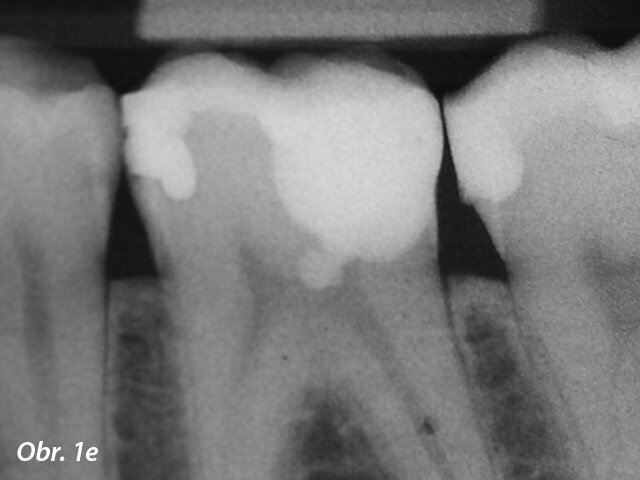

V posledních letech se stala populární terapie zachování vitální pulpy. Běžným materiálem pro překrytí pulpy byl hydroxid vápenatý, ale MTA vykazuje lepší výsledky v biokompatibilitě a úspěšnosti (Aguilar a Linsuwanont 2011). Případy s rozsáhlým kariézním nálezem mohou být úspěšně ošetřeny částečnou pulpotomií a překrytím MTA, což zachová pulpu vitální (obr. 1a–e).

Aplikace MTA s MAP systémem a PD MTA White

Postoperační RTG zobrazující překrytí pulpy s MTA